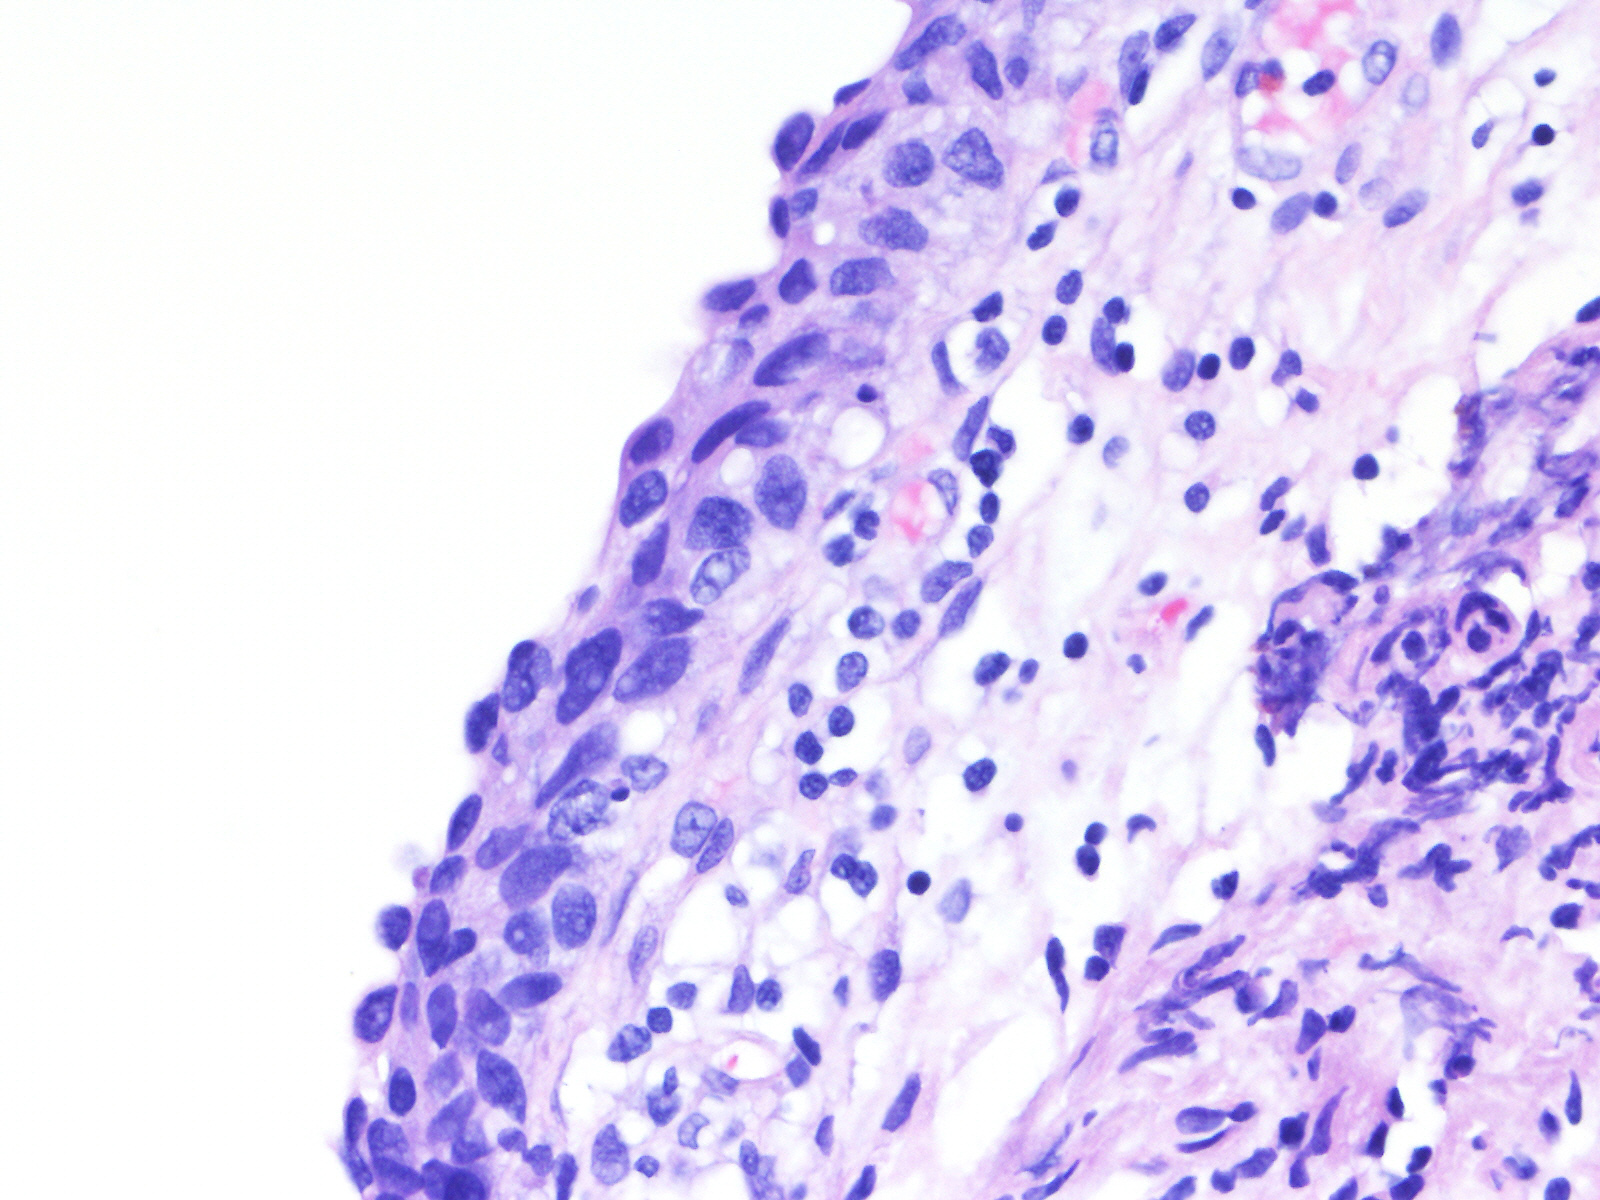

Consensus grade: Carcinoma in situ (CIS)

A 60-year-old female underwent a bladder cystoscopy and biopsy of a 2-cm erythematous lesion at the right posterior bladder wall. About 5 years ago, she was diagnosed with pT1 bladder urothelial carcinoma treated with intravesical therapy.